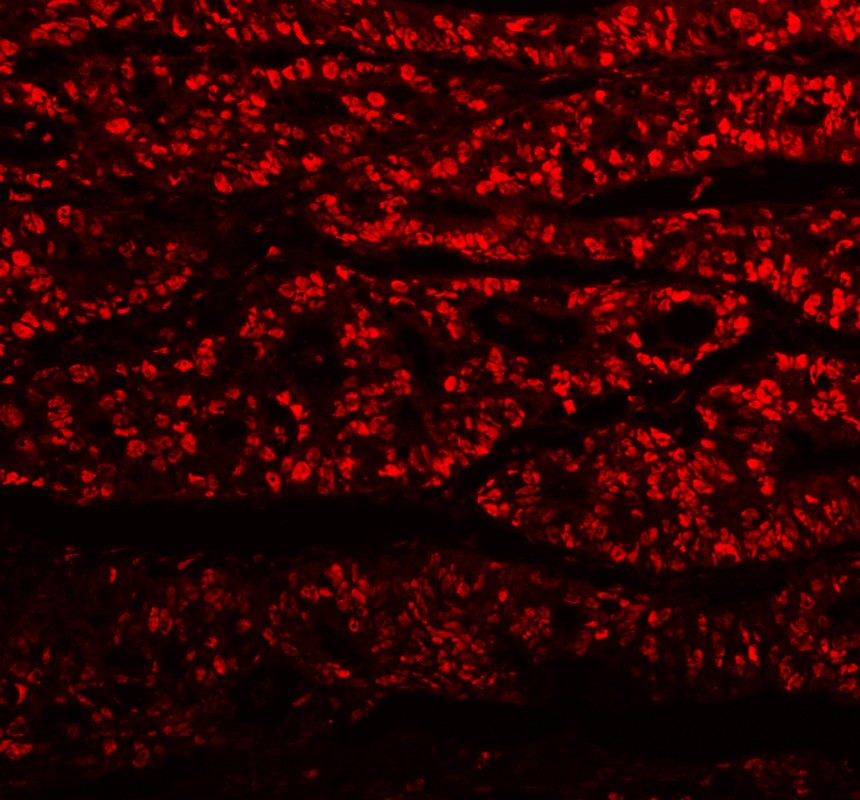

IF analysis of PCNA using anti-PCNA antibody (BM0104).

PCNA was detected in a paraffin-embedded section of human colorectal cancer tissue. The tissue section was incubated with mouse anti-PCNA Antibody (BM0104) at a dilution of 1:100. Fluoro 550 Conjugated AffiniPure Donkey Anti-Mouse IgG (H+L) (red)(Catalog#BA1149) was used as secondary antibody.